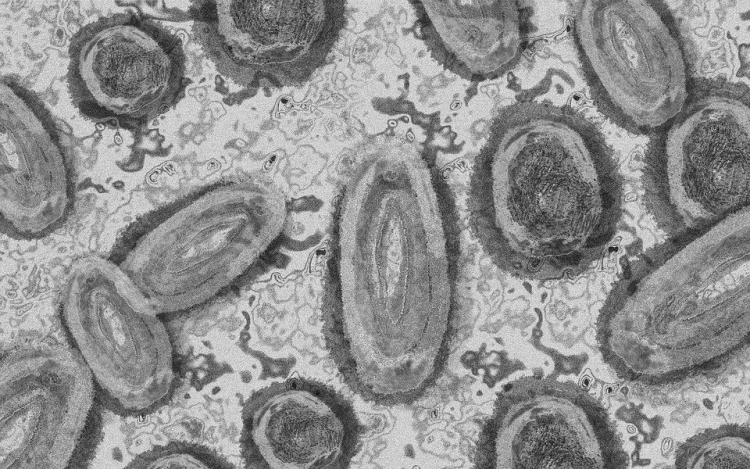

Tovább nőtt a majomhimlő-fertőzöttek száma Magyarországon

Újabb két embernél igazolt majomhimlő-fertőzést a Nemzeti Népegészségügyi Központ (NNK) a 33. héten - augusztus 15-től 21-ig -, ezzel 64-re nőtt a magyarországi esetek száma.

Az NNK pénteki közlése szerint a 22 és a 31 éves férfi általános állapota megfelelő, kórházi kezelés egyikük esetében sem szükséges; otthonukban tartózkodnak elkülönítve.

A területileg illetékes járványügyi hatóság valamennyi betegnél járványügyi vizsgálatot, ennek keretében kontaktkutatást végez - tették hozzá.

Az NNK korábban azt közölte, hogy a betegség általános, nem specifikus tünetekkel - lázzal, hidegrázással, izomfájdalommal, hátfájdalommal, fejfájással, fáradtsággal -, illetve a nyirokcsomók duzzanatával kezdődik, majd 1-3 nappal a bevezető tünetek után bőrkiütések jelennek meg. A kiütések sok esetben először az arcon, majd a tenyéren és a talpon fordulnak elő, de megjelenhetnek a szájnyálkahártyán, a nemi szerveken és a végbél környékén is.